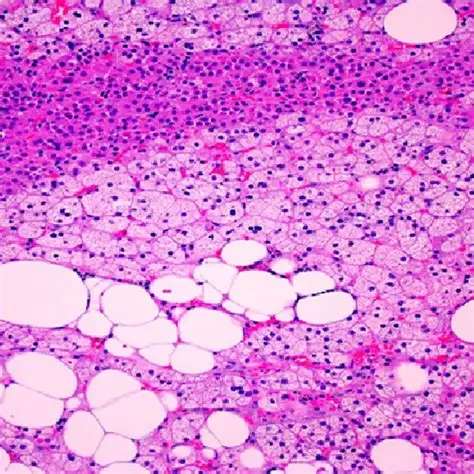

A tirzepatida atua ao reproduzir no organismo a ação de dois hormônios envolvidos no controle do metabolismo e do apetite.

Um deles é o GIP, que estimula a liberação de insulina e contribui para a redução dos níveis de glicose no sangue, além de influenciar a diminuição da fome.

O outro é o GLP-1, responsável por retardar o esvaziamento do estômago e aumentar a sensação de saciedade, o que também leva à redução do apetite.

A semaglutida e a liraglutida agem ao imitar a ação de um único hormônio produzido naturalmente pelo corpo: o GLP-1.

Esse hormônio é liberado principalmente por células do intestino e atua no cérebro, especialmente no hipotálamo, onde participa dos mecanismos de controle da fome, contribuindo para a redução do apetite.

No organismo, o GLP-1 natural tem uma duração curta. Ele é rapidamente inativado pela ação de uma enzima chamada DPP-4, o que faz com que a sensação de fome retorne em pouco tempo.

Já os medicamentos que reproduzem o efeito do GLP-1 foram desenvolvidos para resistir à ação dessa enzima, permanecendo ativos por mais tempo no corpo e prolongando a sensação de saciedade.